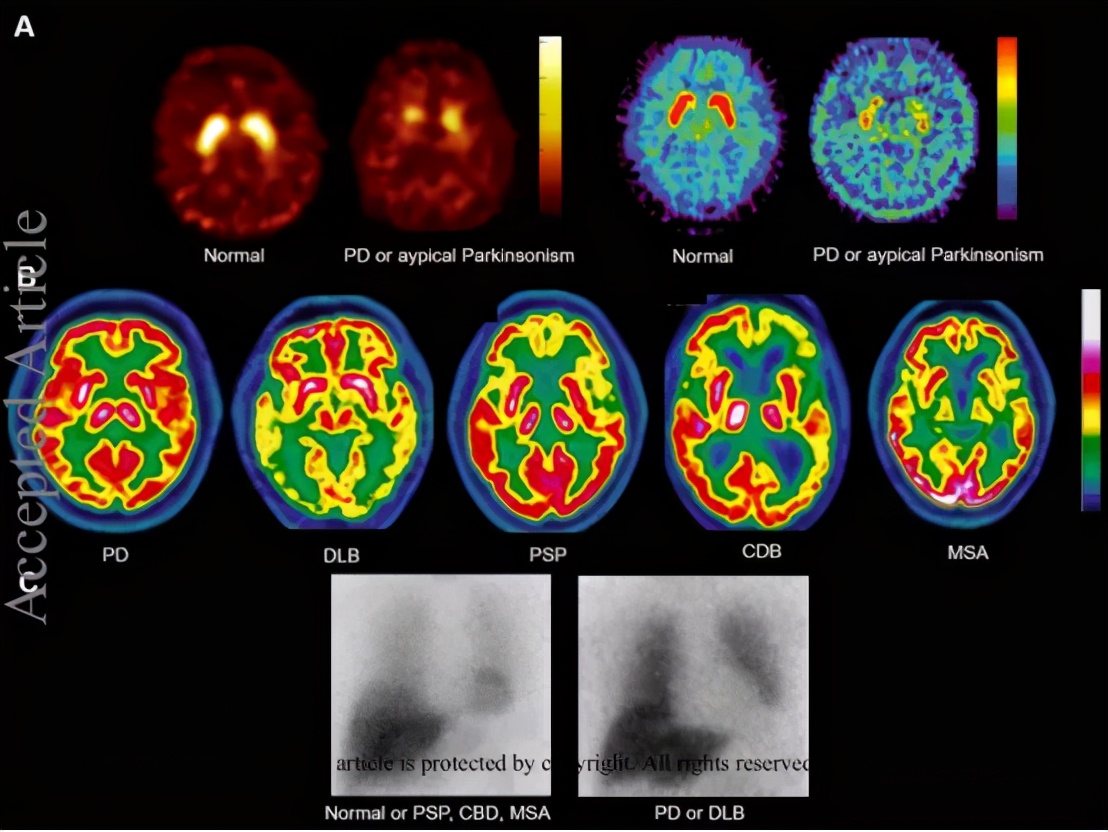

图3:健康人和帕金森病患者SPECT/PET代表性图像

欧洲核医学协会(EANM)和核医学与分子成像协会(SNMMI)最近发布了帕金森症 多巴胺能成像指南 ,描述了两种常用的 检查突触前多巴胺能功能的方法 : 123I标记的多巴胺转运体配体单光子发射计算机断层扫描 (SPECT)和 18F-fluorodopa正电子发射计算机断层扫描 (PET)

这些扫描特征将帕金森氏症与痴呆症、其他形式的帕金森氏症(药物诱发、心因性和血管性帕金森氏症,其诊断需要与MRI图像融合)和特发性震颤做出了区分,还有助于帕金森症的早期诊断。目前, 帕金森综合征SPECT/PET诊断依赖于多巴胺能成像、18F-FDGPET和123I-MIBG闪烁显像的结合。

多巴胺能成像需要考虑放射性示踪剂与药物相互作用。 氟脱氧葡萄糖(18F-FDG)PET和123I间碘苄基胍(123I-MIBG)闪烁扫描也被常规用于评估帕金森综合征(图1)。

18F-FDGPET 显示大脑中糖酵解代谢,比磁共振成像检测到的任何潜在脑萎缩更一致地识别脑功能障碍的显著水平。18F-FDGPET扫描以大于75%的敏感性和90%特异性对帕金森症和帕金森症“plus”综合征进行差异诊断。

123I-MIBG闪烁显像/SPECT显像 以外周交感去甲肾上腺素能储备为目标,区分PD/DLB与认知功能减退和/或帕金森综合征(AD、MSA、PSP、额颞叶和血管性痴呆)的特异性为91%,敏感性为94%。